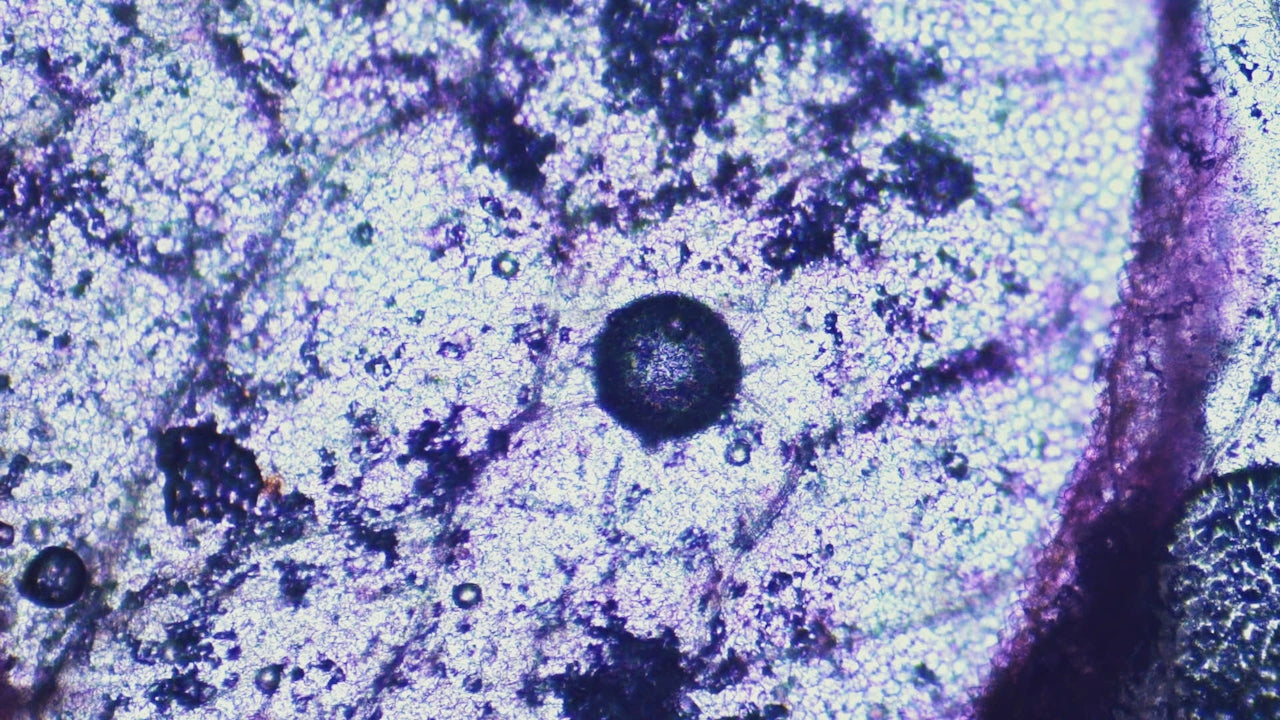

Microbial Fermentation: How Gut Bacteria Turn Fiber Into Function

Microbial fermentation is how gut bacteria convert fermentable fibers into metabolites like short-chain fatty acids. These metabolites are central to gut barrier integrity, immune signalling, and m...